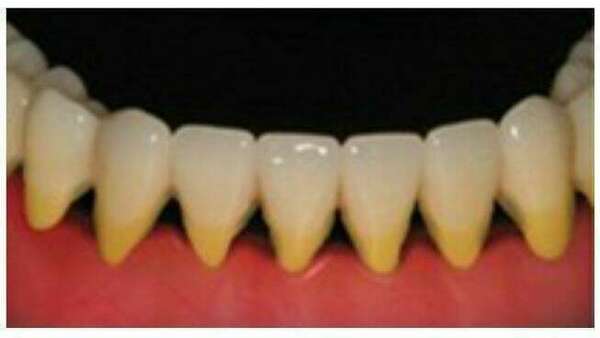

Pour Sauvegarder et Restaurer la dent dans ses fonctions et son esthétique, différentes approches sont nécessaires selon le stade de délabrement :

les restauration sur dents vivantes,

* des atteintes débutantes, par un matériaux inséré en phase plastique: le composite

* des atteintes plus volumineuses, par un matériaux rigide, réalisé sur empreinte: onlay et couronne sur dent vitale